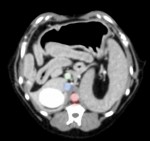

CT検査にて肝臓の器質的変化や門脈体循環シャント(※)がないか確認したのち、肝生検を実施した。

CTでは腫瘤病変など画像診断で検出できる器質的な変化は認められず、シャント血管も認められなかった。